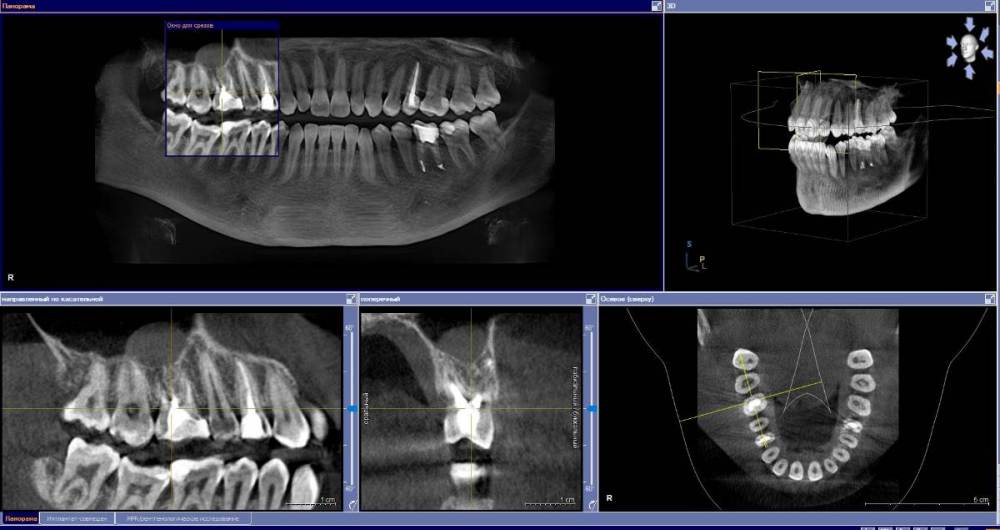

anishuma Опубликовано 1 сентября, 2021 Поделиться Опубликовано 1 сентября, 2021 (изменено) Здравствуйте, прошу помочь разобраться с моими КТ и направить для дальнейших действий. История такая: в 2018 году шестой зуб сверху справа был депульпирован. Долго сохранялись боли при нажатии, при жевании, зуб реагировал на холодной и горячее. Врач, который лечил, заверила что это постпломбировочные боли и скоро пройдет. Коронку побоялась ставить из-за этих болей. Затем примерно через год отлетел кусочек пломбы. Зуб восстановили для дальнейшей установки коронки. На данный момент есть ощутимая реакция на давление, при жевании, при чистки зубной щеткой. Зуб реагирует на холодное-горячее. Один врач сказал, что не видит показаний для перелечивания каналов. Другой врач настаивает на удалении зуба. Подскажите, пожалуйста, где истина, и возможно ли сохранить зуб. Изменено 1 сентября, 2021 пользователем anishuma Ссылка на комментарий

Bier Опубликовано 2 сентября, 2021 Поделиться Опубликовано 2 сентября, 2021 похоже что есть гранулема на корне 2 Ссылка на комментарий

St. Опубликовано 3 сентября, 2021 Поделиться Опубликовано 3 сентября, 2021 +1 к гранулеме. Я бы перелечивала каналы. Но нужно в процессе будет смотреть нет ли трещин в корне. Ссылка на комментарий